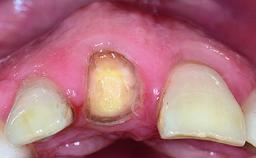

A 32-year-old female Caucasian patient with a compromised maxillary right central incisor was referred to us by a general dentist. Her chief complaints were discomfort and mobility of tooth 11 with unsatisfactory esthetics due to discoloration. The patient reported a previous trauma, some years earlier, as the origin of pathology on the afflicted tooth. Anamnesis was negative for any other dental or periodontal pathology in the remaining dentition. The patient did not take any medication and reported to be a light smoker (5–10 cigs/day). She had high esthetic expectations of her treatment. The extraoral examination revealed a high smile line with full exposure of her maxillary teeth and surrounding soft tissue in the area between the second premolars.

Provisional Implant-Supported Prosthesis Prosthodontic margin > 3 mm apical to mucosal margin Prosthodontic margin > 3 mm apical to mucosal margin

Interim Prosthesis during Healing Fixed Fixed